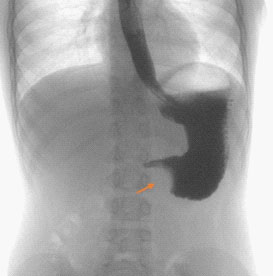

Upper gastrointestinal tract series showed a large, round filling defect of 3,3 cm in diameter, with regular shapes and located between the gastric antrum and pylorus (Figure 1).

Figure 1:Radiographic findings of upper gastrointestinal tract – A mass was protruding into the gastric lumen causing a stomach filling defect at the passage between antrum and pylorus.